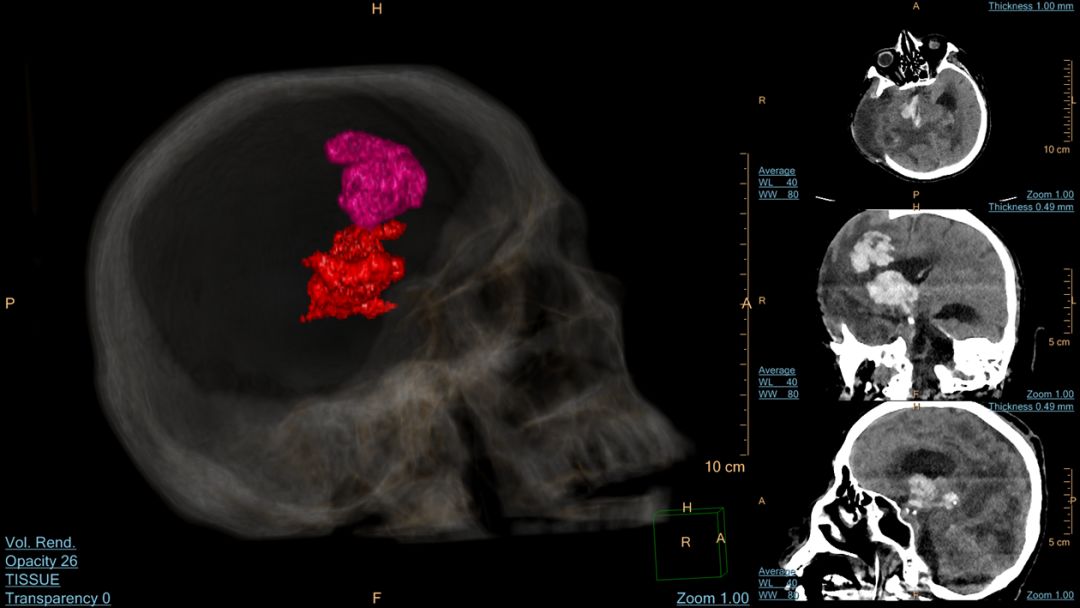

脑出血VR重建图像

脑出血染色

脑出血与颅骨半透明融合

患者,男,60岁,脑部术后复查

患者脑部术后,颅内脑出血形态不规则,且分布广泛,对于脑出血量的计算,原始的手动计算方法无法正确评估,飞利浦星云工作站操作方便,1分钟内精准测量复杂脑出血体积,并且对脑出血的形态、位置等作出立体显示,为临床治疗提供全方位影像信息。